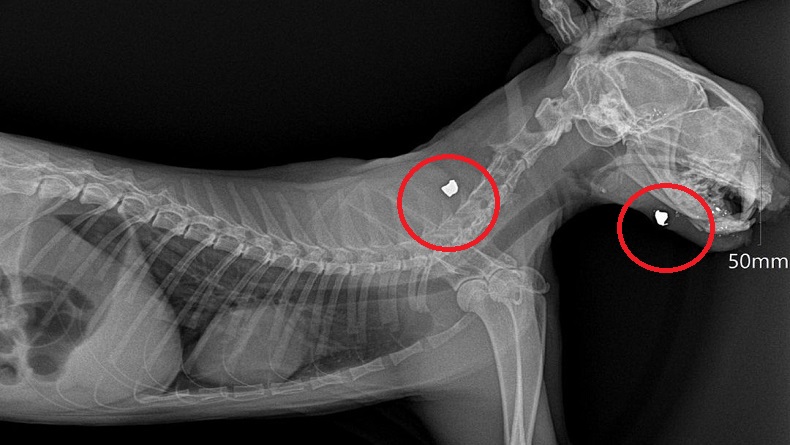

Luka tembak (lingkaran merah) ditemukan di leher dan kepala kucing yang mati di sekitar Markas Sesko TNI. (FOTO: tangkapan layar)

BANDUNG, iNews.id - Enam ekor kucing yang ditembak mati di sekitar Markas Sesko TNI Bandung, Jalan Martanegara, Kecamatan Lengkong, Kota Bandung, mengalami luka di kepala dan leher. Berdasarkan pemeriksaan X-ray, peluru bersarang di duga bagian tubuh itu.